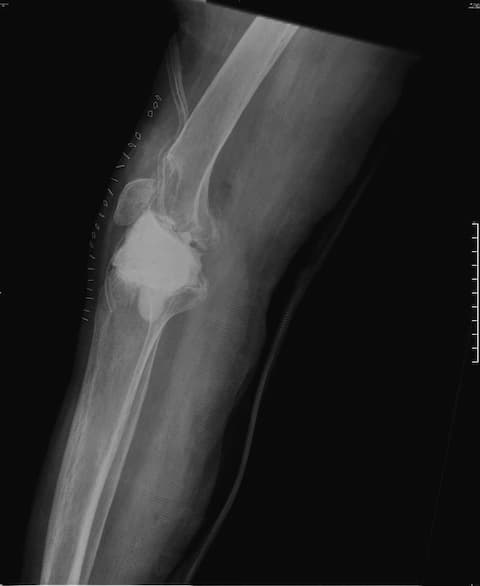

Үе дайрсан ясны анхдагч хавдар, ясны дутмагшлын үед хийгдэх мэс засалimg22Үе дайрсан ясны анхдагч хавдар, ясны дутмагшлын үед хийгдэх мэс засалimg23

Зураг 1. Сэргээн засах мэс заслын өмнөх рентген зураг. Эгц урд, хажуугаас авсан байдал.